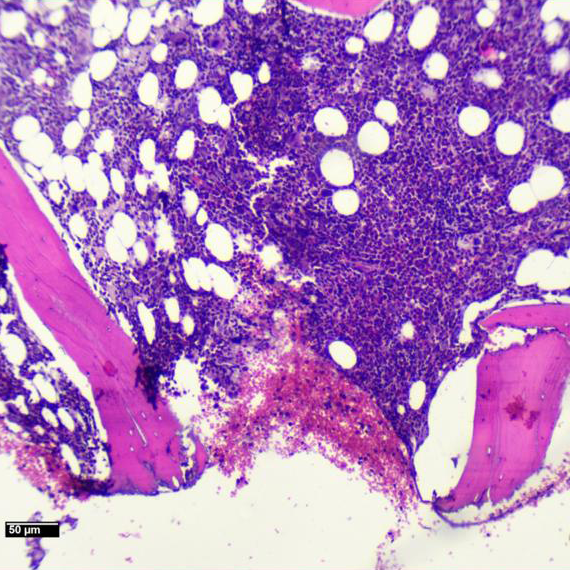

Se realiza punción de médula ósea.

Imágenes Microscopio

MÉDULA ÓSEA HIPERCELULAR CON CAMBIOS CITOPÁTICOS COMPATIBLES CON INFECCIÓN POR PARVOVIRUS

• La morfología típica muestra una médula ósea hipocelular, no como en este caso; pero las características citológicas de los eritroblastos, resaltadas en la coloración de Giemsa, que muestran macrocariosis e inclusiones nucleares; apoyadas por los hallazgos de la PCR confirman el diagnóstico.